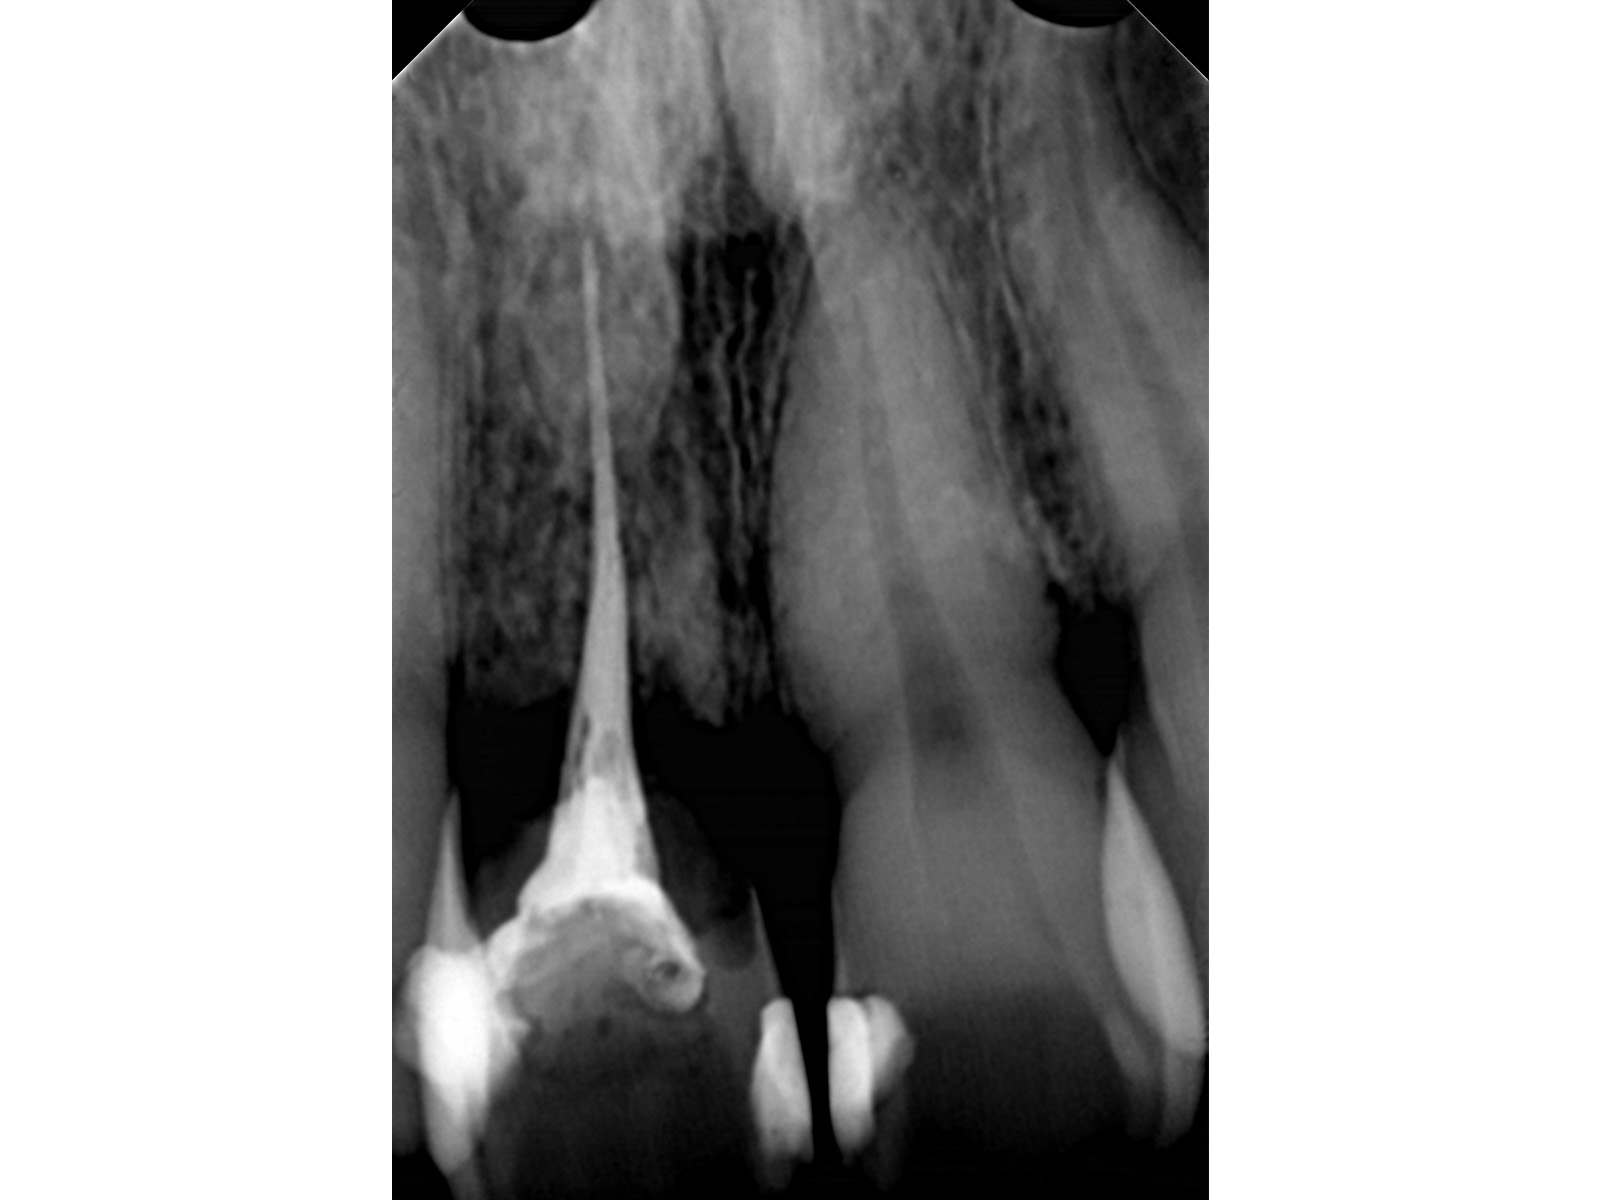

主訴: 8年前の事故でぶつけて歯根吸収していた為、前突・叢生が気になる。

右上中切歯 抜歯後、空隙を閉鎖しました。

左右下 第一小臼歯2本、左上 第一大臼歯1本、右上 前歯1本を抜歯。

・抜歯した右上前歯の隣りの歯を抜歯してあいたスペースで移動。